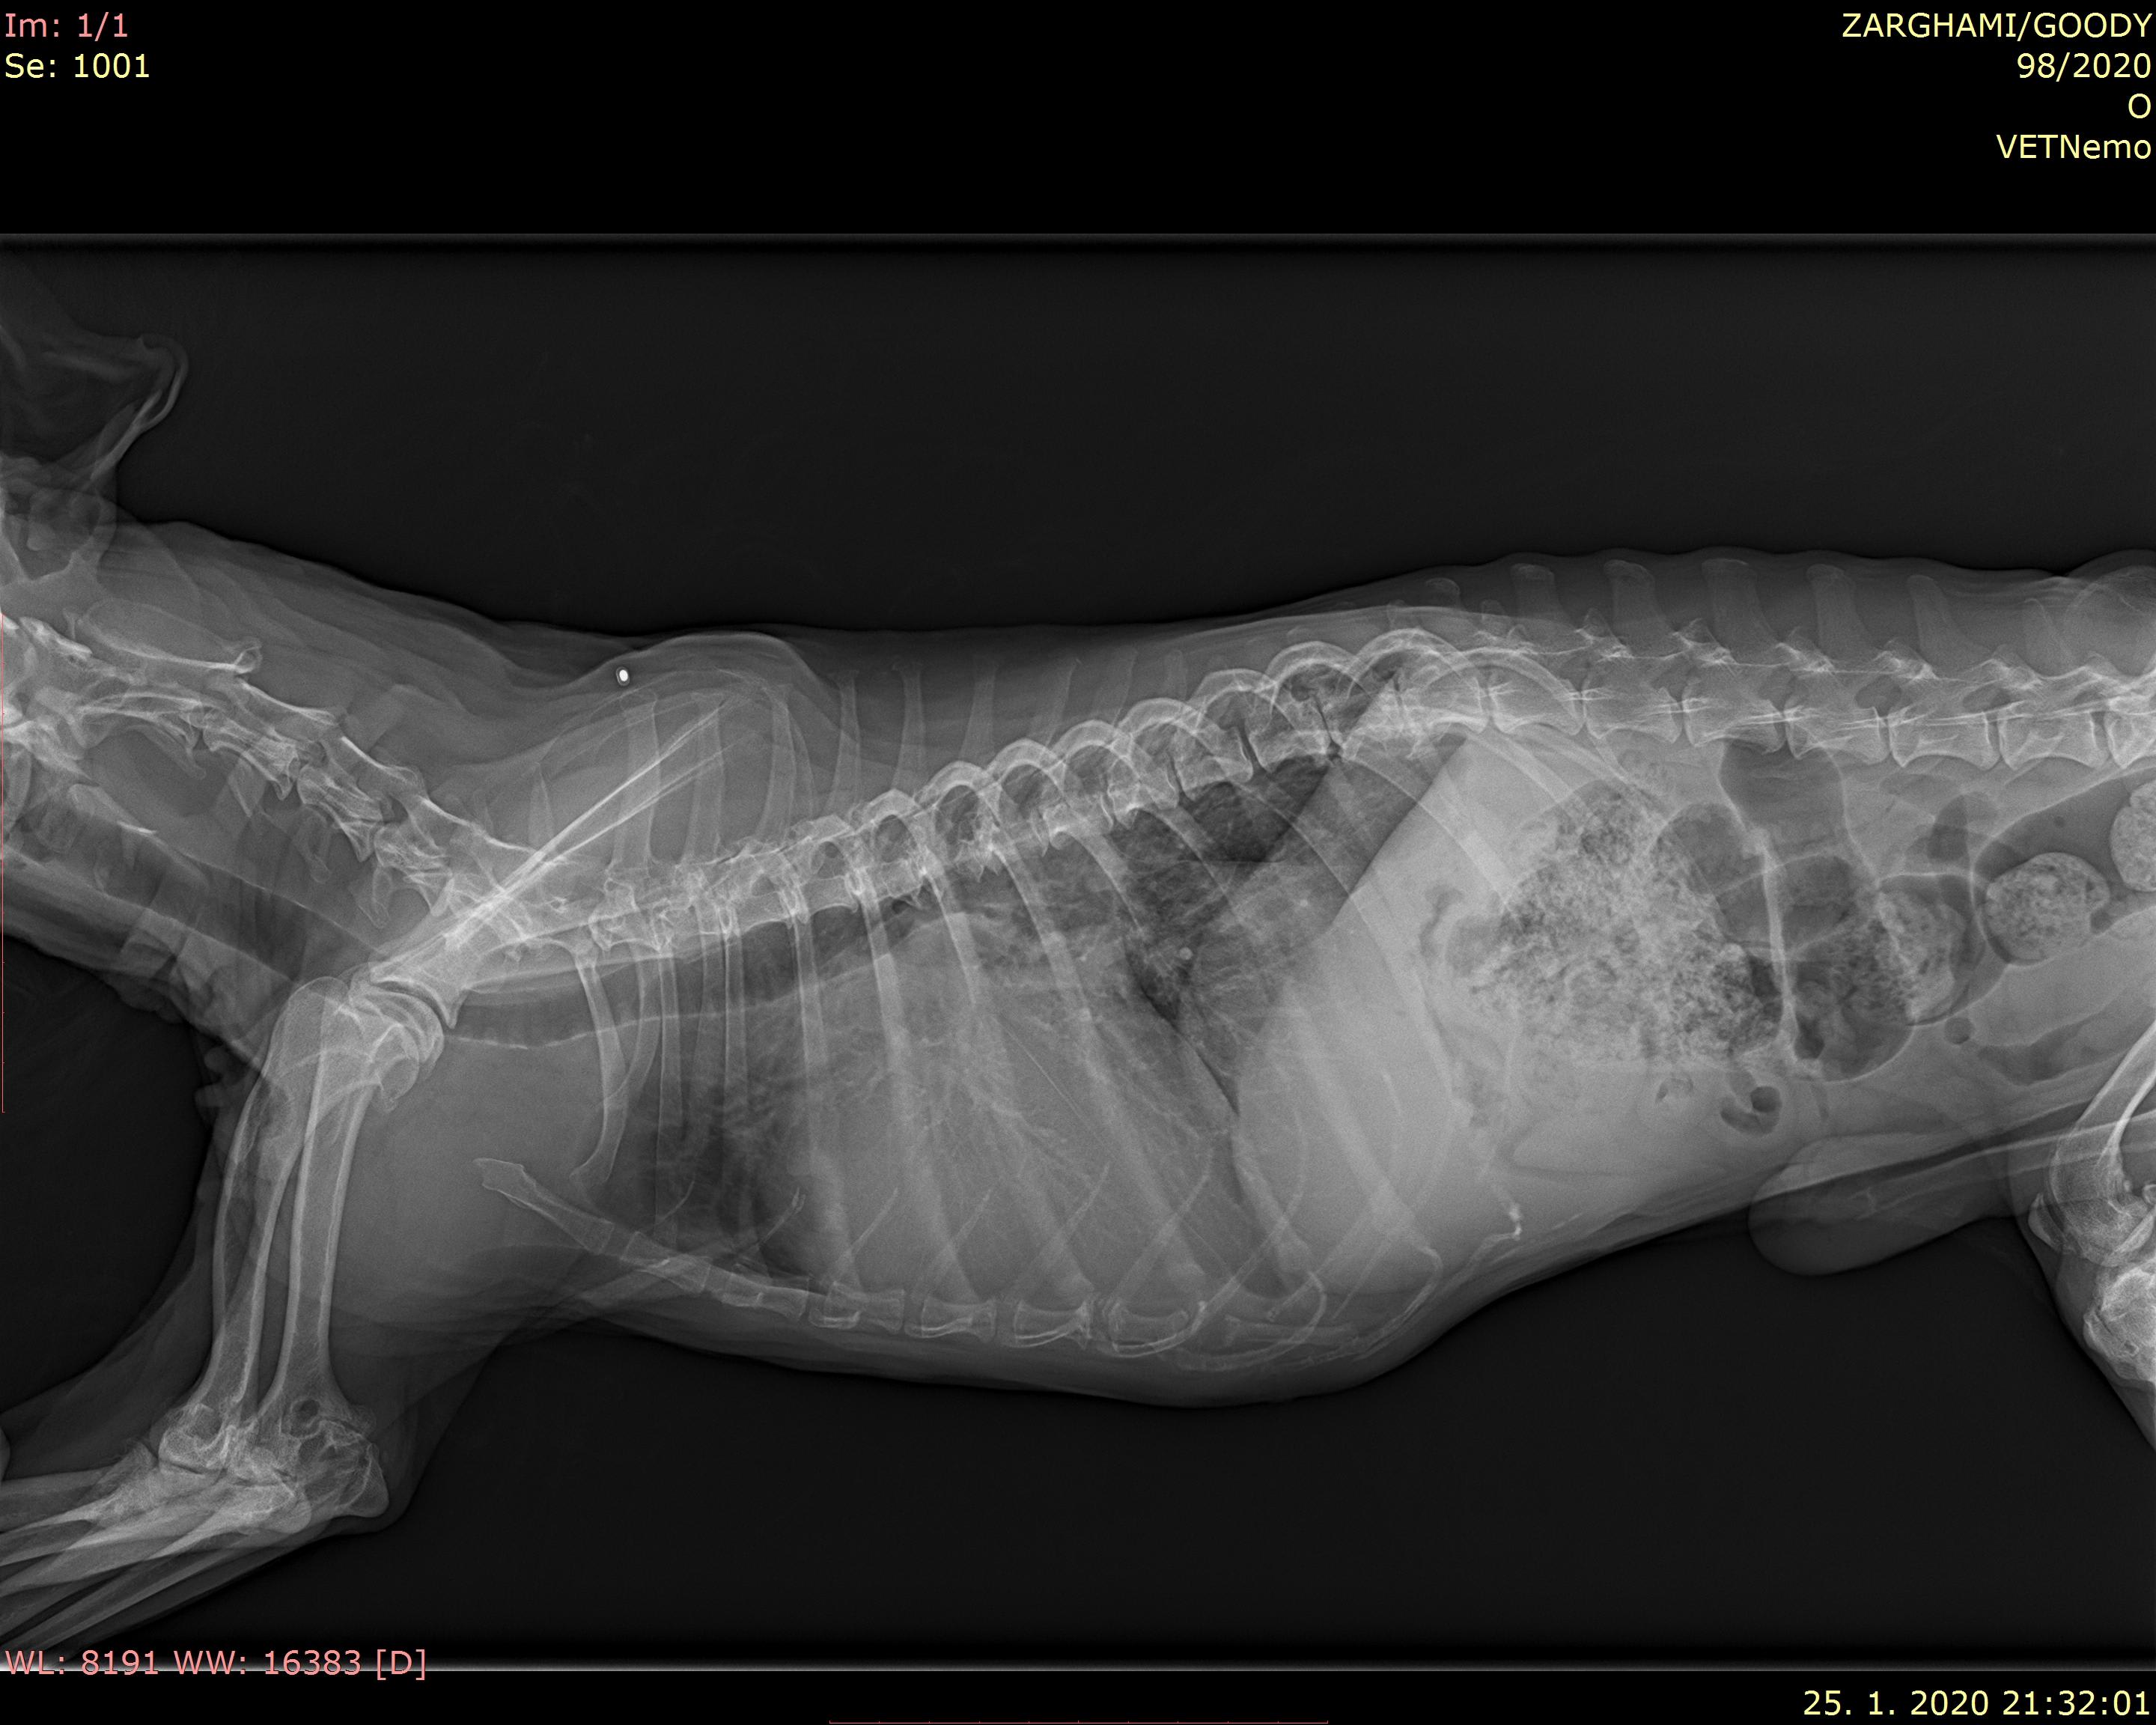

Hello there, I have a terrier senior dog, he is 15 and 8 month,he is suffering from heart failure, he uses several medicine like vetmedin 1.25mg , cordarone200mg 1 quarter morning and one quarter in the evening, upcard 0.75mg 1 in the morning and half in the evening and virospiron 25mg 1quarter a day,but since previous week he starts frequent coughing ,he has a sever shortness breathing tonight and drinking water more. here is tonight X-ray the vet said there is no pulmonary.please advice me

Your dog has severe heart enlargement. For this reason, it is pressing his windpipe (trachea) upward and causing a narrowing which is the likely cause of his cough. Unfortunately, there's no way to prevent this. Ideally, you would keep him as quiet as possible and minimize his activity/stress. Your vet is correct, it doesn't look like he has pulmonary edema. You may want to consider medication to keep him more relaxed to prevent excessive coughing.